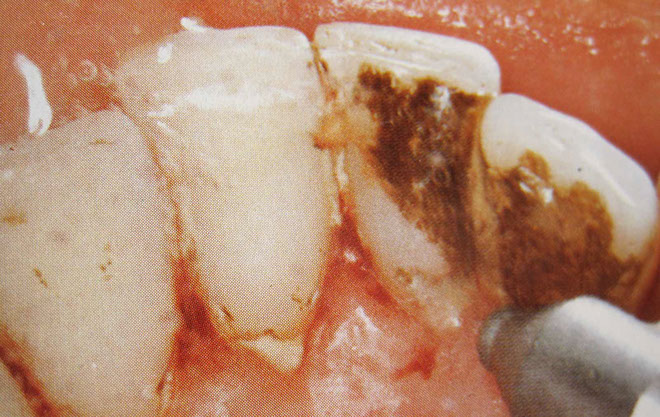

In the first step of cleaning, tartar and plaque are removed from the teeth using ultrasound and Airflow®. The spaces between the teeth are then flossed and cleaned.

Solid deposits, which often form below the gingival margin, are gently removed with special instruments. Gum pockets are also rinsed and disinfected.